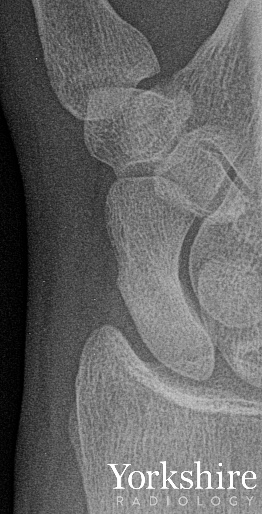

This is why we use MRI in patients with suspected scaphoid fractures who remain symptomatic - despite apparently normal radiographs. #FOAMed #FOAMrad #orthotwitter

Small fracture - big injury. The radiograph shows a small avulsion fragment, commonly known as a Segond fracture. Well over 90% of patients with this finding will also have an ACL rupture. Learn more about knee anatomy and injuries @arthroinsights #FOAMed #FOAMrad #orthotwitter